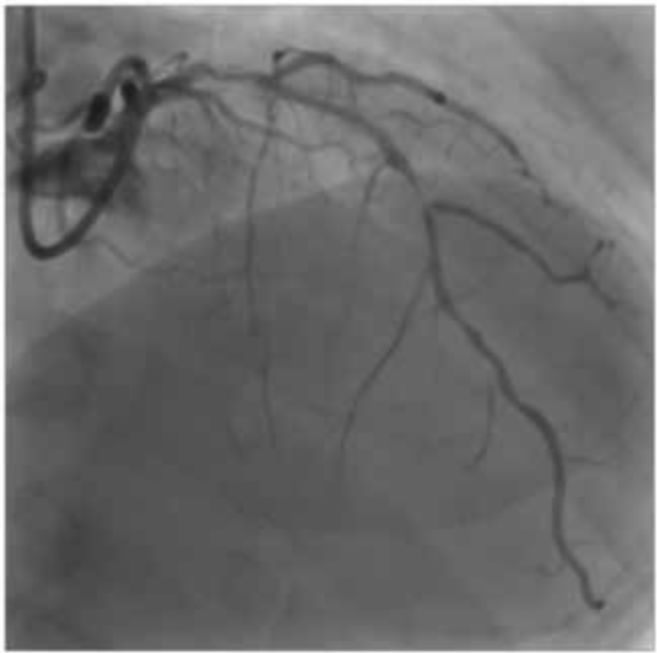

治疗过程:右侧桡动脉穿刺,前次的造影导管为JL4.0,因为左主干短,所以使用ASAHI导引导管6Fr JL4.0 ST SH。LCA开口靠后,由于搭冠很困难,所以将导管从鞘内退出,将导管头端沿逆时针方向扭转并定形。然后在导管顶到左冠窦时逆时针旋转,LCA搭冠成功。(图2